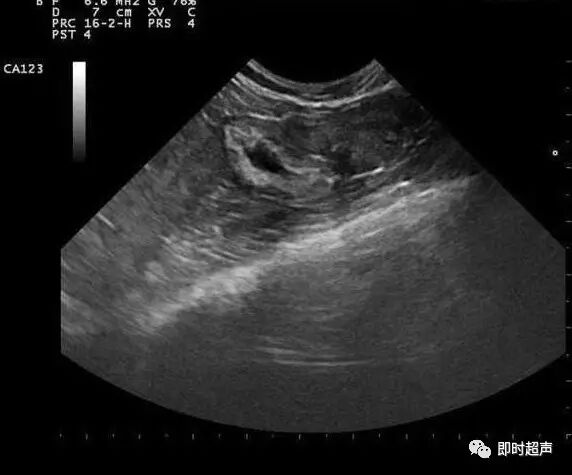

B超是产检的重要内容之一,但是有些胎儿异常是B超也是检测不出来的。几乎所有胎儿的内脏器官,在出生前都会持续不断的成长变化,因此并非在早期检查时,为正常状况的器官,就能保证在出生后也一定正常。那么,哪些胎儿缺陷B超检查不出来?下面就随小编一起来看看。

这8种胎儿缺陷B超检查不出来

1水脑

有许多水脑或水肾的状况,都会到了怀孕后期才逐渐产生。

2全盲

胎儿在子宫内因为没有光线的刺激,因此不会睁开眼睛,所以无法诊断出先天全盲或小眼症的状况。

3听力

在胎儿5-6个月大时,听力已有发育,但目前没有任何的方式可以得知,胎儿是否有先天性听障的问题。

4先天心脏病

心脏的心房中隔(即卵圆孔),以及动静脉导管,都是在出生后才会逐渐关闭,虽然是在出生便可轻易诊断出的心脏病,却无法在出生前就得知。

5肠胃道阻塞

肠胃道的阻塞病变,极少数会出现在怀孕24周之前,因为胎儿在怀孕前期,很少大口的吞进羊水。

6肢(指、趾)端异常

像是手脚内翻或外翻、多指(趾)、并指或指节缺失等异常状况,也因为胎儿常处于握拳状态,几乎无法由超音波确切诊断。

7侏儒症

有部分的侏儒症状,无法在早期诊断出来。因为胎儿在6-7个月大的时候,就会逐渐停止骨头的发育生长。

8先天性代谢异常

绝大部分的生化代谢异常疾病,例如黏多醣症,都要等到宝宝出生进食后,才会逐渐发病。也因此许多致死性的生化代谢异常,在产前无法辨认,除非妈妈已生过类似疾病的宝宝。